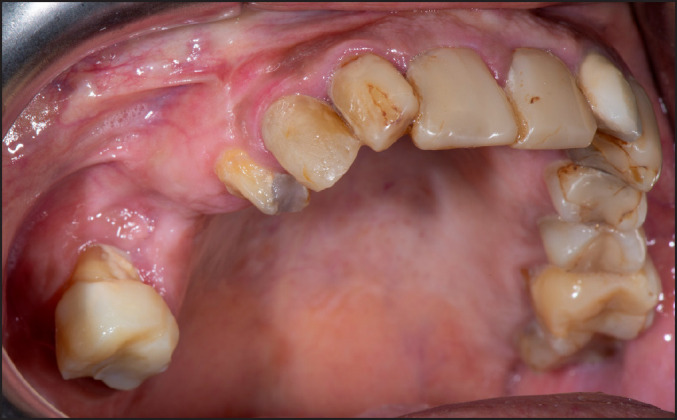

Methods: A female patient, 62 years old, was referred to the Department of Dentoalveolar Surgery, Surgical Implantology and Radiology, School of Dentistry, Aristotle University of Thessaloniki, Greece, complaining about pain in the first quadrant. Her medical history revealed per os bisphosphonate administration for the past four years. Subsequently, the cone-beam computed tomography examination revealed a small sequestrum of bone, surrounded by radiolucency, in proximity with the sinus floor. The clinical examination didn't reveal any pathological clinical signs.